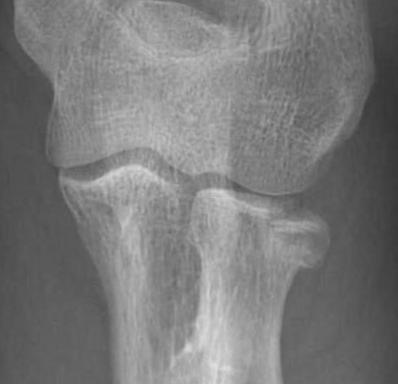

Overstuffing

| Lesser sigmoid notch | Symmetry of ulnohumeral joint |

|---|---|

|

Radial head shoulder articulate with lesser notch

Ensure no gapping of lateral ulnohumeral joint |

- cadaveric study

- increased medial ulno-humeral joint line gapping with overlengthening of 6 or 8 mm

- increased lateral ulno-humeral joint line gapping with overlengthening of 2 mm